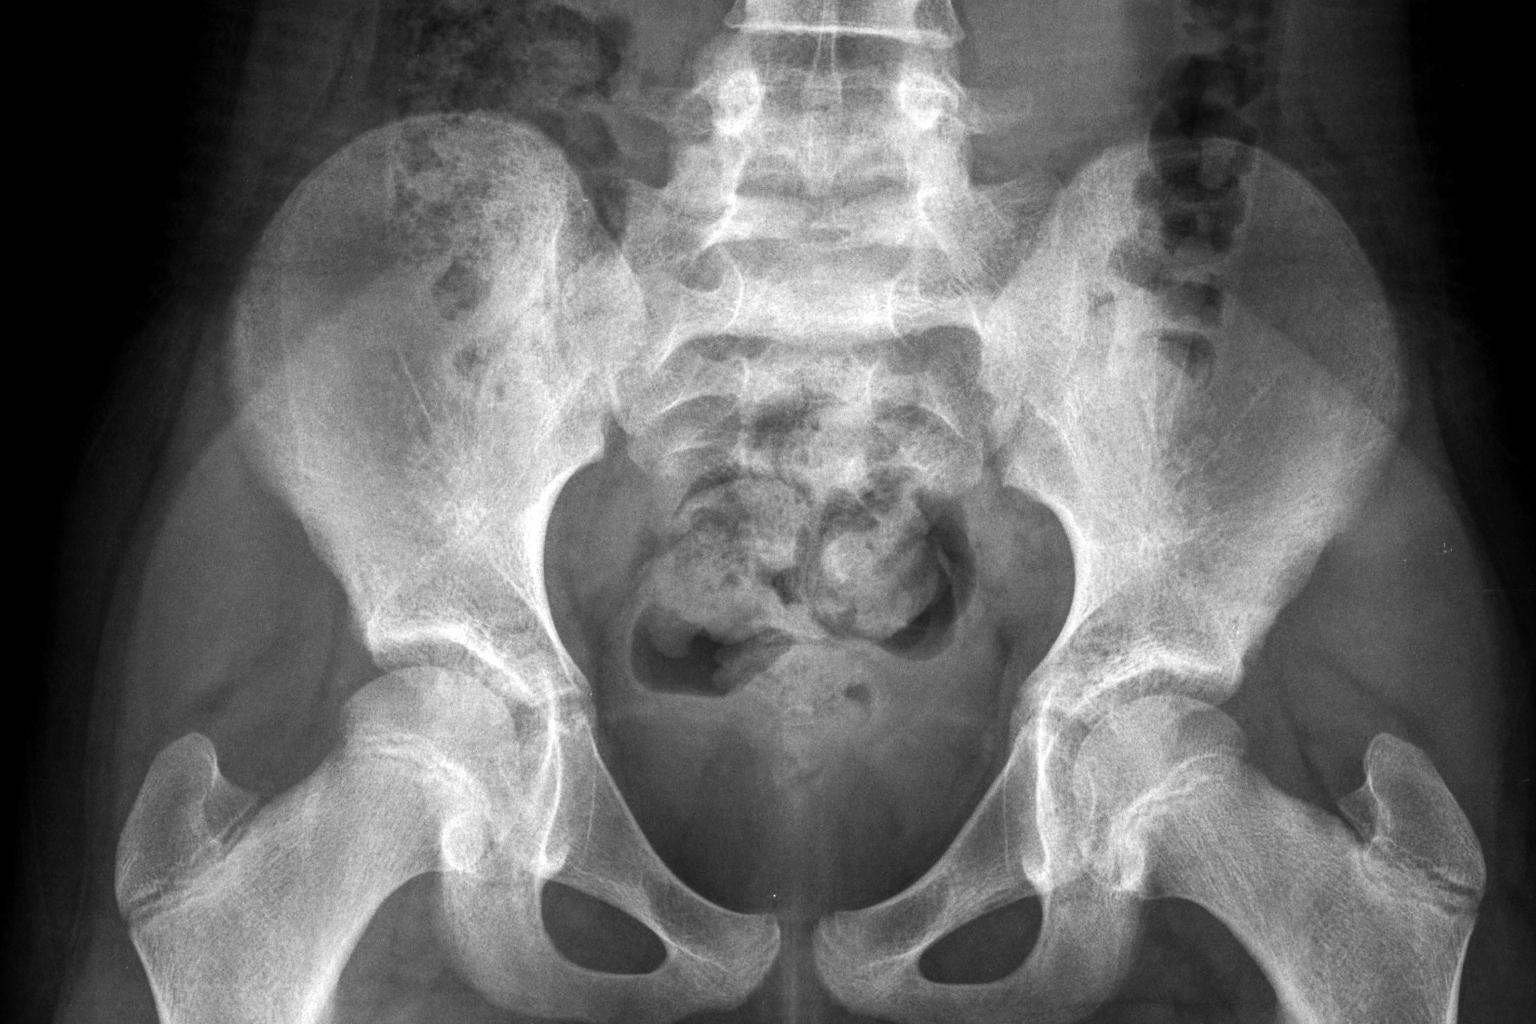

An X-ray of a healthy 10-year-old girl.

PHOTO: NYTIMES

The critical issue is that the pelvis of a child is too small to allow the passage of even a small foetus, said Dr Ashok Dyalchand, who has worked with pregnant adolescent girls in low-income communities in India for more than 40 years.